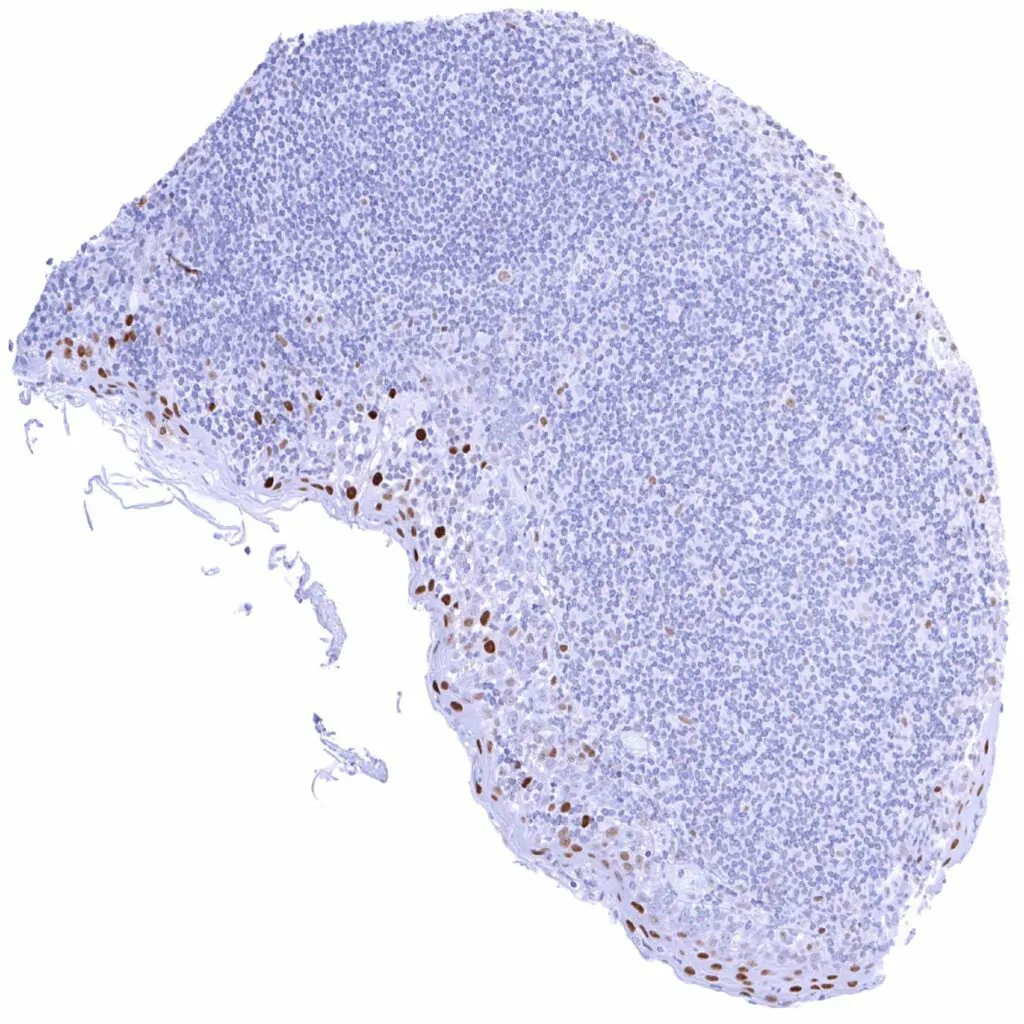

Thymus – Strong Cyclin E1 staining of some regularly distributed cells (thymic epithelial cells_). Weak Cyclin E1 staining of some lymphocytic cells

Tonsil – Weak to moderate Cyclin E1 staining of a fraction of lymphocytic cells, especially in germinal centres